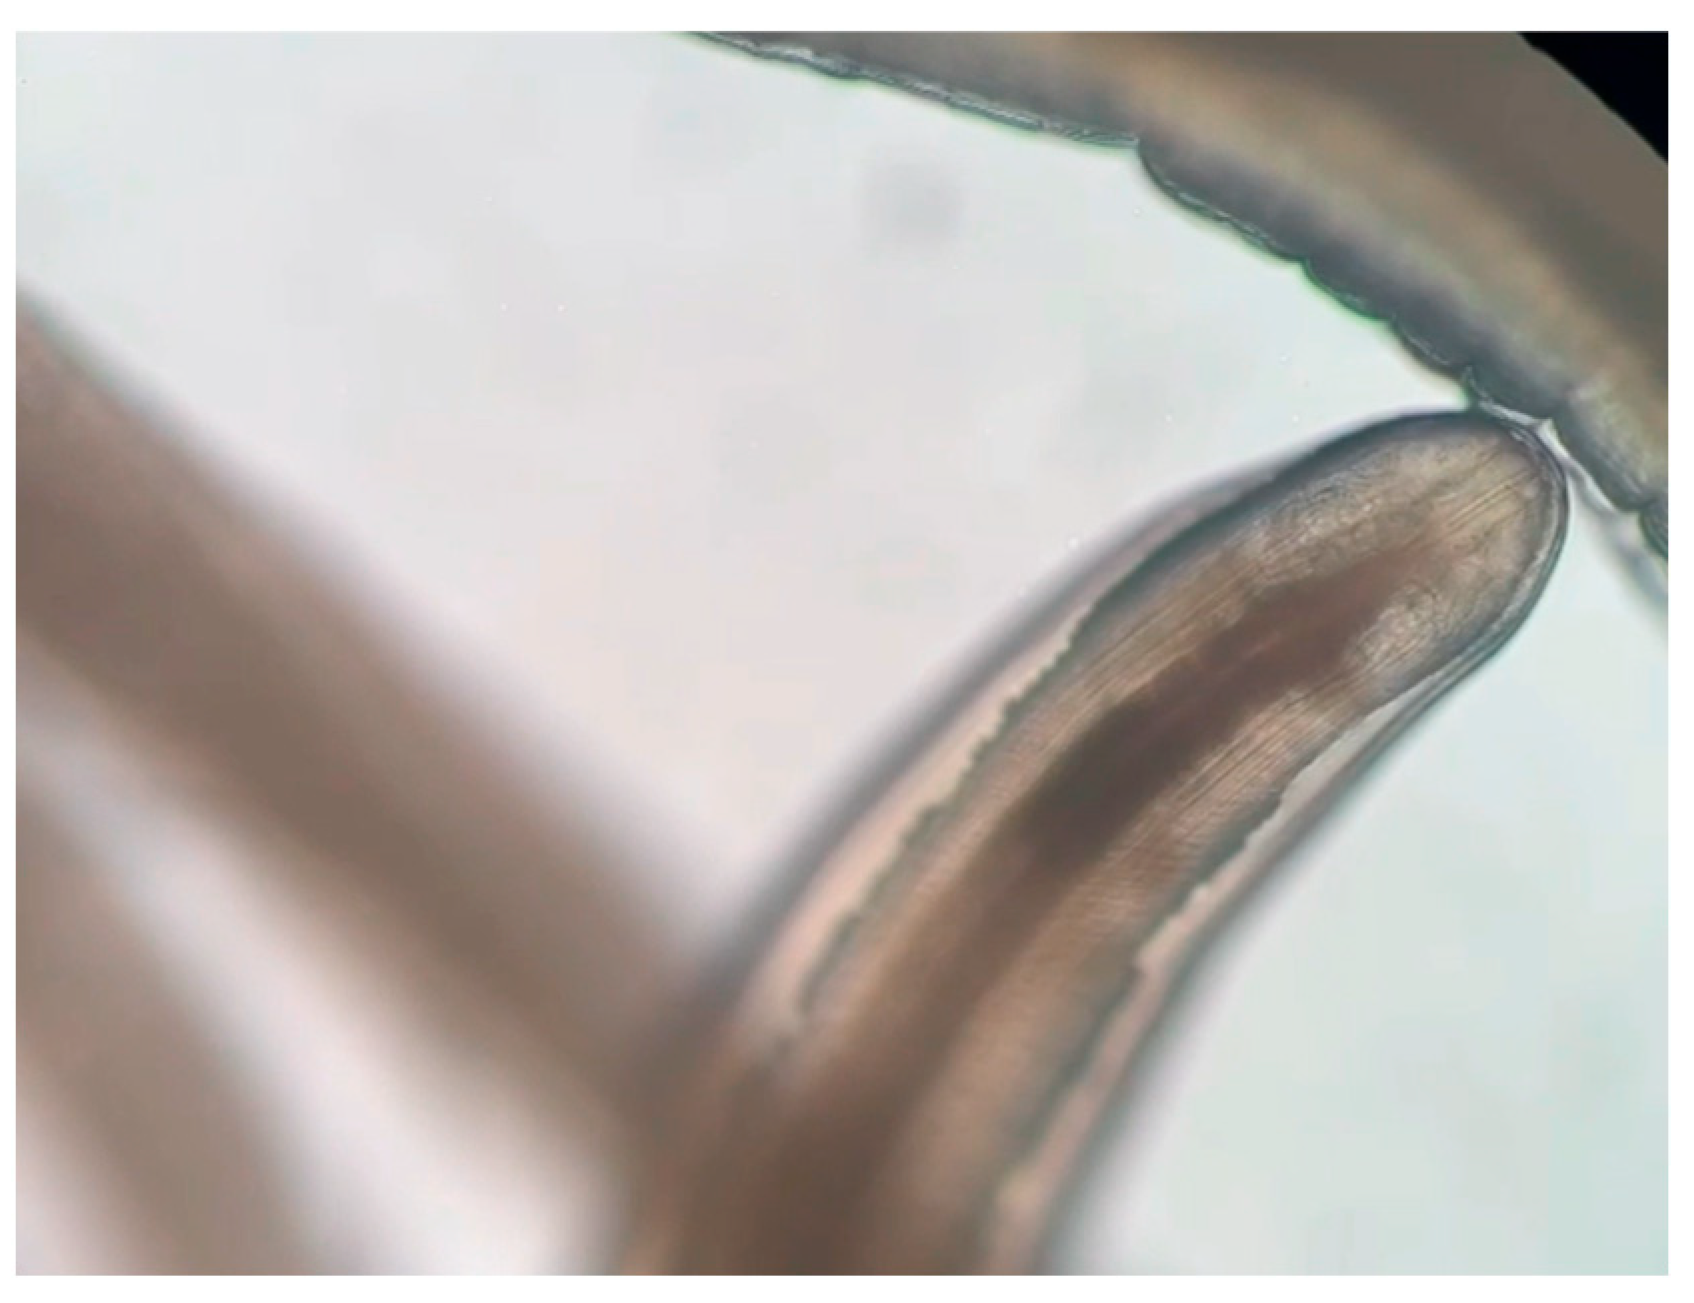

3.1. Morphology